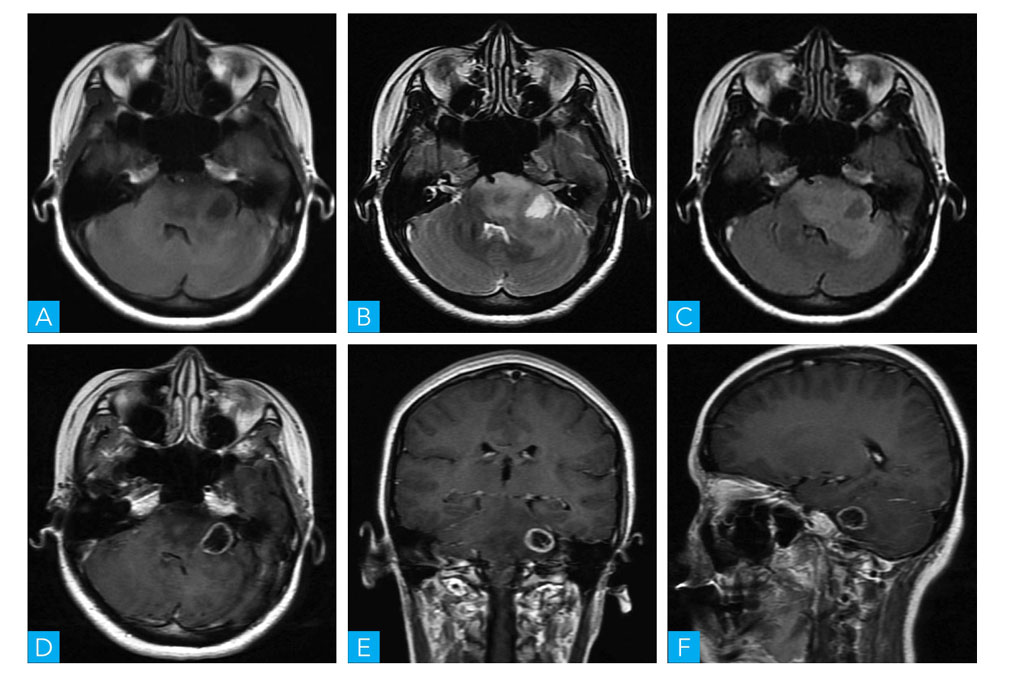

图1-1-4 桥小脑角区脑膜瘤MRI扫描

A.轴位T1WI;B.轴位T2WI;C.轴位T2-FLAIR;D.轴位T1WI增强

是桥小脑角区发病率位居第二的肿瘤,常以宽基底与邻近硬脑膜紧密相连,CT表现为等或稍高密度,增强扫描可见明显强化,邻近颅底局部骨质可见增生或骨质吸收改变;MRI表现为T1WI呈等信号或略低信号,T2WI为高信号,但不及听神经瘤高,病灶与脑实质分界较清晰,增强后呈均匀一致强化,可出现“脑膜尾征”,周围脑实质无水肿或轻度水肿。部分脑膜瘤可发生钙化、囊变、坏死或出血,导致信号不均匀(图1-1-4)。

(3)桥小脑角区表皮样囊肿:

亦称胆脂瘤,是桥小脑角区第三大常见的占位性病变。表皮样囊肿为起源于外胚层的先天性病变,可能是由于神经管闭合时外胚层残余所致。CT表现为匍匐式生长的低密度影,增强扫描未见强化。MRI表现为形态不规则的异常信号影,T1WI为稍低信号,T2WI为明显高信号,与脑脊液信号相仿,该病特征是在DWI上呈高信号表现,病变呈匍式生长,沿脑沟脑回呈塑形发展,可包绕血管及神经;因病变内无血管,因此增强后不强化(图1-1-5)。

图1-1-5 桥小脑角区表皮样囊肿MRI扫描

A.轴位 T1WI;B.轴位 T2WI;C.轴位 DWI;D.轴位 T1WI增强